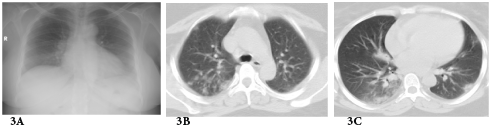

Graft failure occurred in 2 patients; one of them had already high serum creatinine at diagnosis (3mg/dl) and started dialysis 1year after H1N1 infection while the other has normal serum creatinine at diagnosis (1mg/dl) and was presented 1year later due to unexplained graft dysfunction. Some authors believe that influenza virus is capable of activating immunologic mechanisms leading to allograft rejection.9 The activation of such immunological mechanisms is related to production of interleukin -1, TNF, IL-6 and IL-8 during viral replication.10 The time interval for incidence of H1N1 infection started from the second half of December till the second half of January. Other series documented the incidence between the second half of July up to September in Asia (Singapore)8 while the largest number of confirmed cases of 2009 influenza A (H1N1) infection in North America occurred between March and July 2009.11 H1N1 infections has many complications in RTR including respiratory, cardiac and CNS sequences. However, the most common prescribed complication among RTR in the literature is respiratory complications. In one of early reports described 2 RTR that developed hypoxic respiratory failure and necessitated noninvasive ventilation12 while Singapore report described 2 mortalities among 10 cases of pneumonia.8 Other complications included H1N1 related myocarditis13 or encephalitis.14 In our series, only respiratory complications were encountered as previously mentioned. Our cases have excellent prognosis, most probably due to early initiation of oseltamivir therapy, doubling the dose and extension of the duration of treatment. Also temporary reduction of anti-proliferative drug may help RTR to recover early. Three cases of pneumonia showed inconclusive CXR while CT chest revealed bilateral infiltrates and this signifies the importance of CT chest in diagnosis of pneumonia in immune-compromised patients see Figure 3. Serial CXR was carried out to follow up lung recovery in cases of H1N1 pneumonia and it was correlated with the clinical response (Figure 4). The suspected number of RTR in December -2009 was 36 RTR which is double the number of suspected number in December-2010,this may be due to two facts; the first is vaccination with seasonal and novel H1N1 vaccine while the second is familiarity of criteria of diagnosis which reduced the number of suspected RTR.

Figure 4A Chest X-ray film on day two from suffering attack of low grade fever.

Figure 4B Follow up Chest X-ray at time of diagnosing H1N1 pneumonia 6 days later.

Figure 4C Follow up Chest X-ray three days after starting oseltamivir therapy.

Figure 4D Follow up chest X-ray after 7 days from starting H1N1 therapy.

Figure 4E Follow up Chest x-ray showing further improvement.

Figure 4F Follow up chest X-ray 4 days after the end of H1N1 therapy.

Figure 4 H1N1 radiological pictures in a diabetic 28-year-old transplant recipient.